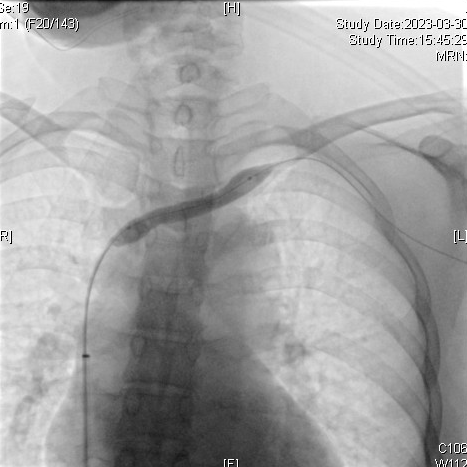

【病例分享】郭明金教授团队:Venovo静脉支架在左头臂静脉闭塞病变中应用

主诉:左上肢肿胀疼痛1周。

查体:左上肢肿胀,张力高,左前胸壁肿胀,可见胸壁静脉曲张,左腕部可见切口,切口下可触及震颤,左前臂、左上臂分别较对侧粗6cm、8cm。

诊断:1、左头臂静脉闭塞,2、慢性肾衰竭尿毒症期,3、高血压。